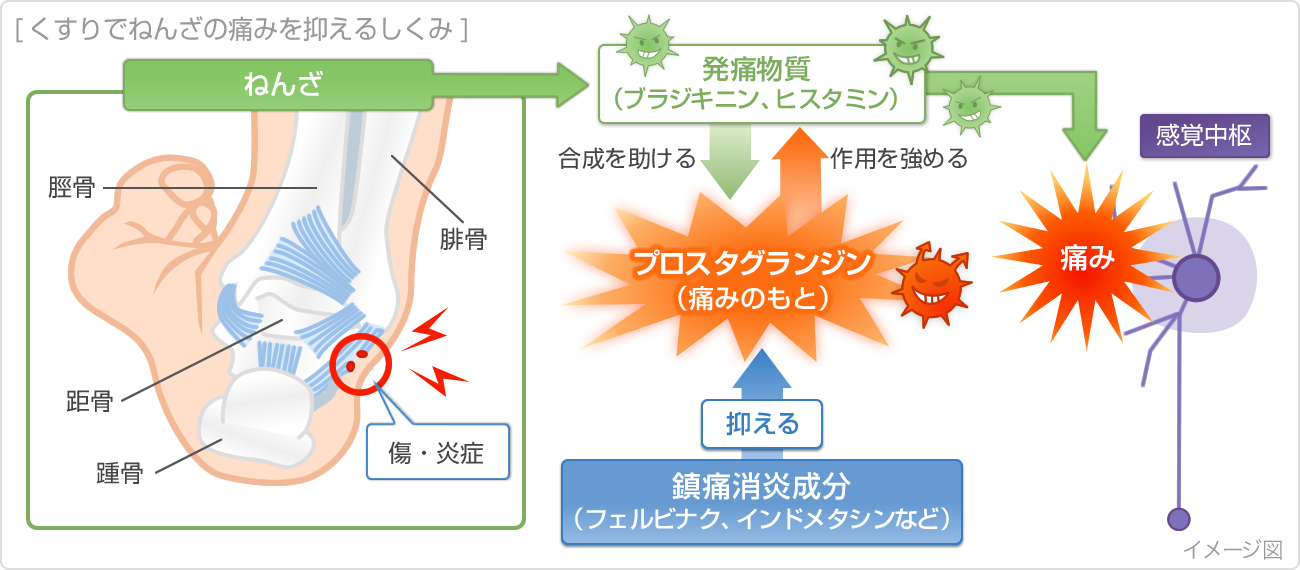

足首の捻挫を一瞬で治す方法 足首の捻挫を一瞬で治す方法 Watch later Share Copy link Info Shopping Tap to unmute If playback doesn't begin shortly, try捻挫(ねんざ)に湿布(シップ)は効果がある? 風邪薬や胃薬の様に湿布(経皮吸収型鎮痛消炎剤)を常備薬として持っている方も多いのではないでしょうか。 湿布(シップ)は身近な医薬品で江戸時代から使われていると言われています。 冷感タイプだけでなく、温熱タイプや様々な鎮痛成分の含まれた湿布もあります。 これらの湿布は捻挫に対して効果が · 足首まで浸かるくらいの氷水が望ましいです。 できなければ、氷嚢・ビニール袋に氷を詰めたもので冷やしましょう! 捻挫をした時は、直ぐにでもアイシングをすると、後の治る速度・日数を大幅に短縮できます。

捻挫 ねんざ の対策 くすりと健康の情報局

捻挫 ねんざ の症状 原因 くすりと健康の情報局